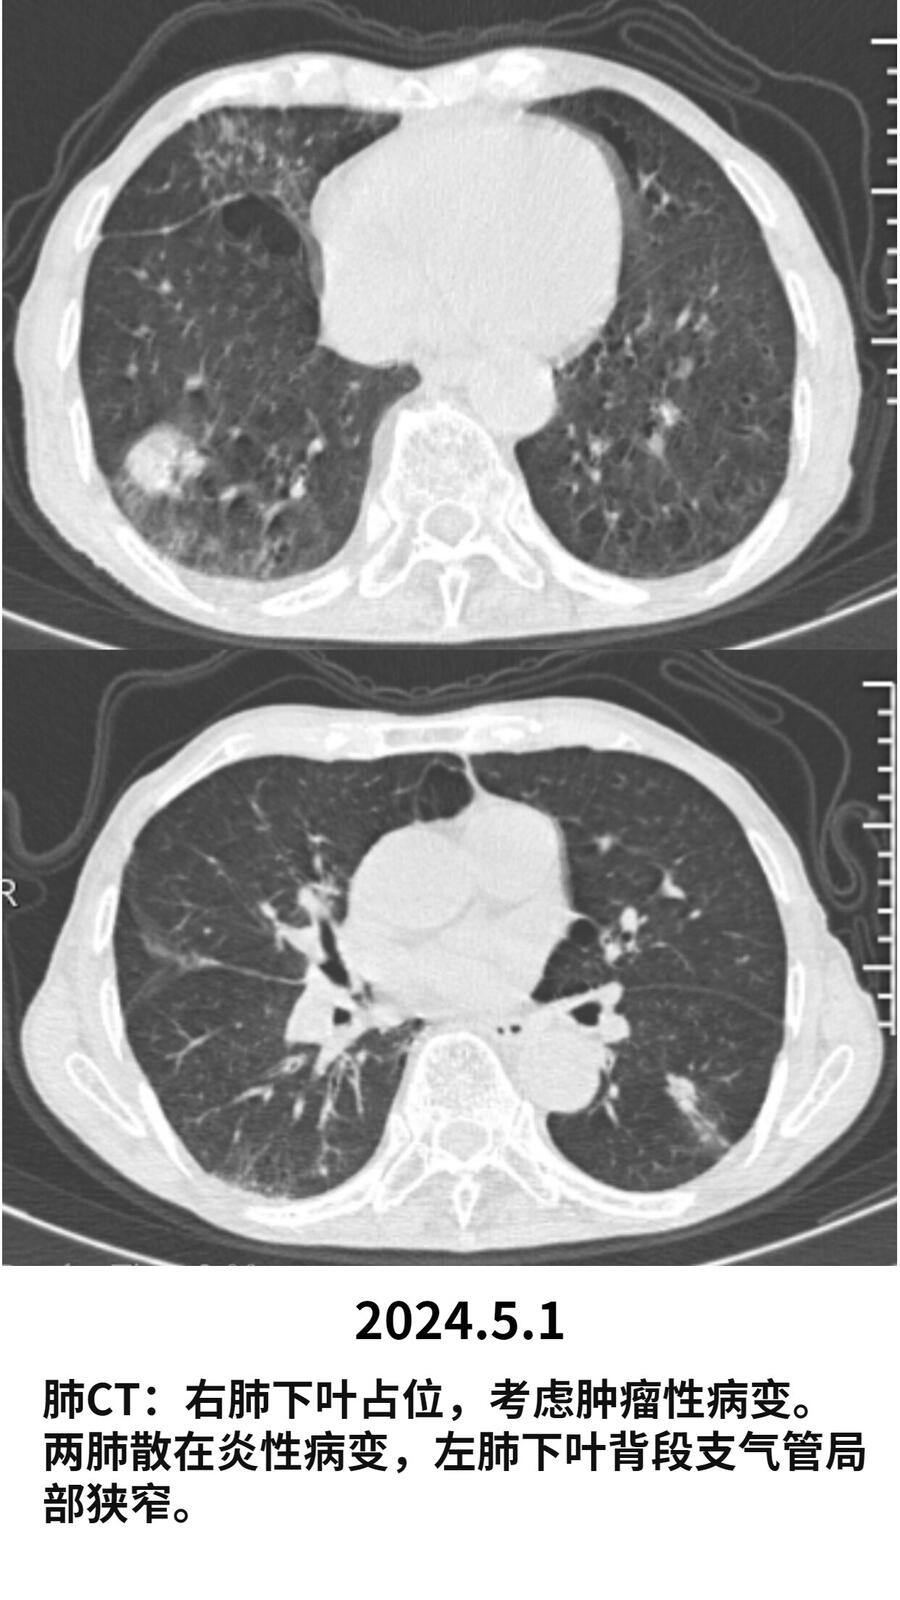

2024.1患者肺CT提示右肺下叶占位,大约3*3cm.高度怀疑恶性肿瘤。